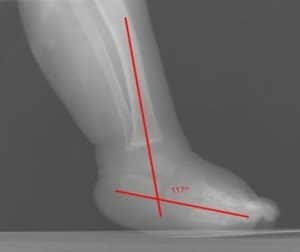

Figure 2: Lateral view in talipes equinovarus demonstrates an abnormally elevated tibiocalcaneal angle (Normal angle is 60-90°)

Talocalcaneal parallelism is the radiographic feature of clubfoot (talipes). Simulated weight-bearing X-rays are used for infants who have not commenced walking. Positioning for foot x-rays is very important. The anteroposterior (AP) view is taken with the foot in 30° of plantarflexion and the tube at 30° from vertical. The lateral view is taken with the foot in 30° of plantarflexion. AP and lateral views can also be taken in full dorsiflexion and plantarflexion. This is especially essential in determining the total amount of dorsiflexion completed at the end of treatment, as well as the relative positions of the talus and calcaneum.

Measure the talocalcaneal angle in the AP and lateral films. AP lines are drawn through the center of the long axis of the talus (parallel to the medial border) and through the long axis of the calcaneum (parallel to the lateral border), and they usually subtend an angle of 25-40°. Any angle less than 20° is considered abnormal. The AP talocalcaneal lines are almost parallel in clubfeet. As the feet are correct with casting or surgery, the calcaneus rotates externally, and the talus reciprocally also derotates to a lesser degree to give a convergent talocalcaneal angle. Lateral lines are drawn through the midpoint of the head and body of the talus and along the bottom of the calcaneum, usually 35-50°. Clubfoot ranges between 35° and –10°.

The lateral talocalcaneal lines are almost parallel in clubfeet. As the feet are correct with casting or surgery, the calcaneum dorsiflexes relative to the talus to give a convergent talocalcaneal angle. These two angles, AP and lateral, are added to derive the talocalcaneal index, which in a corrected foot should be more than 40°. The AP and lateral talar lines normally pass through the center of the navicular and the first metatarsal.